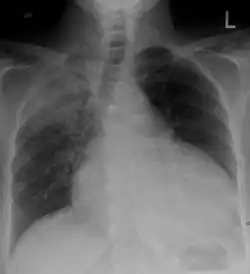

Chest x-ray: is non-specific and may not help identify a pericardial effusion but a very large, chronic effusion can present as "water-bottle sign" on an x-ray, which occurs when the cardiopericardial silhouette is enlarged and assumes the shape of a flask or water bottle.[2] Chest radiograph is also helpful in ruling out pneumothorax, pneumonia, and esophageal rupture.

- Pericardial effusion due to malignancy. Note bulbous heart and primary lung cancer in right upper lobe.